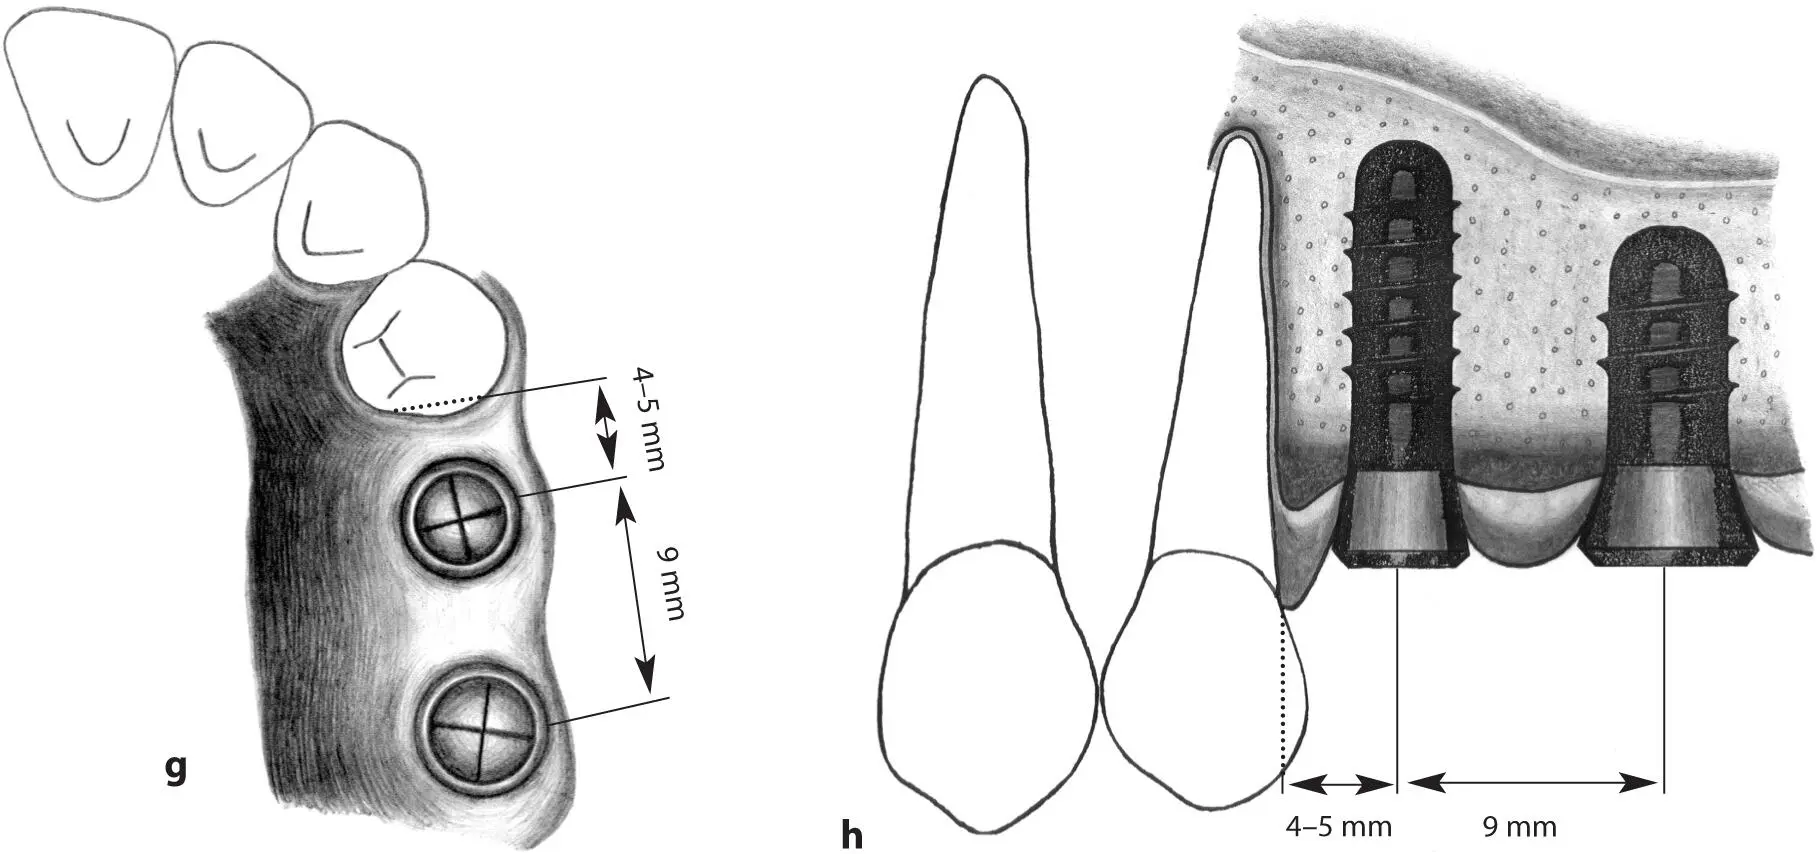

Figs 1-11g and 1-11h Occlusal (g) and lateral (h) views of regular neck and wide neck implants. When a regular neck implant and a wide neck implant are indicated to replace a missing second premolar and molar, the regular neck implant should be placed 4 to 5 mm from the tooth and the wide neck implant placed approximately 9 mm from the anterior implant.

Figs 1-11i and 1-11j Occlusal (i) and lateral (j) views of implants positioned in the first premolar and first molar sites. In this extended posterior distal extension situation, a regular neck implant and a wide neck implant are indicated as abutments for a three-unit fixed partial denture. The regular neck implant is positioned 4 to 5 mm from the tooth. The wide neck implant is inserted about 16 mm from the anterior implant.